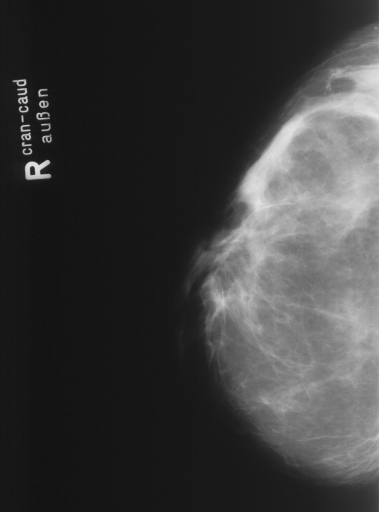

In this series of experiments, we randomly selected three categories from IRMA dataset (namely, breast, foot and lung), and for each category we choose 5 random images from that class (Figures 5, 6 and 7 show these images). When we find “4 out of 180” (4/180) and “8 out of 180” (8/180) projections via micro-DE (tasks that cannot be performed via brute-force), then the question is what can we say about the reconstruction error, in terms of correlation between original and reconstructed images, when we compare evolutionary approximation with the case that we can manage via exhaustive search, namely “4 out of 16” (4/16)? Can micro-DE reach at least the same correlation (similarity) as the brute-force case in lower dimensions? If yes, we may have more confidence in using micro-DE in practice where we cannot apply brute force for benchmarking or direct use, especially for higher dimensions (i.e., the number of projections).

For finding optimal projections based on micro-DE (4 out of 180), we set the parameters of micro-DE to be NFC, , , , and we run each experiment 30 times. For optimal projections based on micro-DE (8 out of 180), we set NFC, , , , and we run each experiment 30 times. The results are presented in Tables 2, 3 and 4. In all cases, micro-DE (MDE) with 4/180 reaches the same correlations as brute force (BF) for 4/16. Of course, MDE finds different projections as it is searching the entire search space of . However, that the same level of reconstruction accuracy can be achieved establishes the reliability of MDE as a practical solution that may even produce a higher-level of uniqueness for Radon barcodes as 4 projections are selected among all 180 angles (the increased uniqueness needs to be verified by applying the Radon barcodes for image retrieval). On the other hand, MDE for 8/180 clearly increases the correlation with statistical significance. This is very encouraging as we can generate more expressive Radon barcodes using a higher number of projections.

| image | BF (4/16) | MDE (4/180) | MDE (8/180) | |||

|---|---|---|---|---|---|---|

| f1 | [11,45,135,169] | 0.61 | [20,40,140,170] | 0.59 | [180,170,30,90,10,90,40,120] | 0.65 |

| f2 | [11,67,112,169] | 0.66 | [30,170,70,110] | 0.66 | [70,70,100,140,20,20,160,170] | 0.70 |

| f3 | [11,67,112,169] | 0.69 | [10,30,120,170] | 0.68 | [30,50,100,110,80,10,150,180] | 0.72 |

| f4 | [22,78,112,157] | 0.59 | [20,80,120,160] | 0.60 | [70,40,10,150,180,90,50,130] | 0.66 |

| f5 | [22,78,101,169] | 0.58 | [20,90,130,170] | 0.61 | [110,140,40,20,90,80,170,10] | 0.65 |